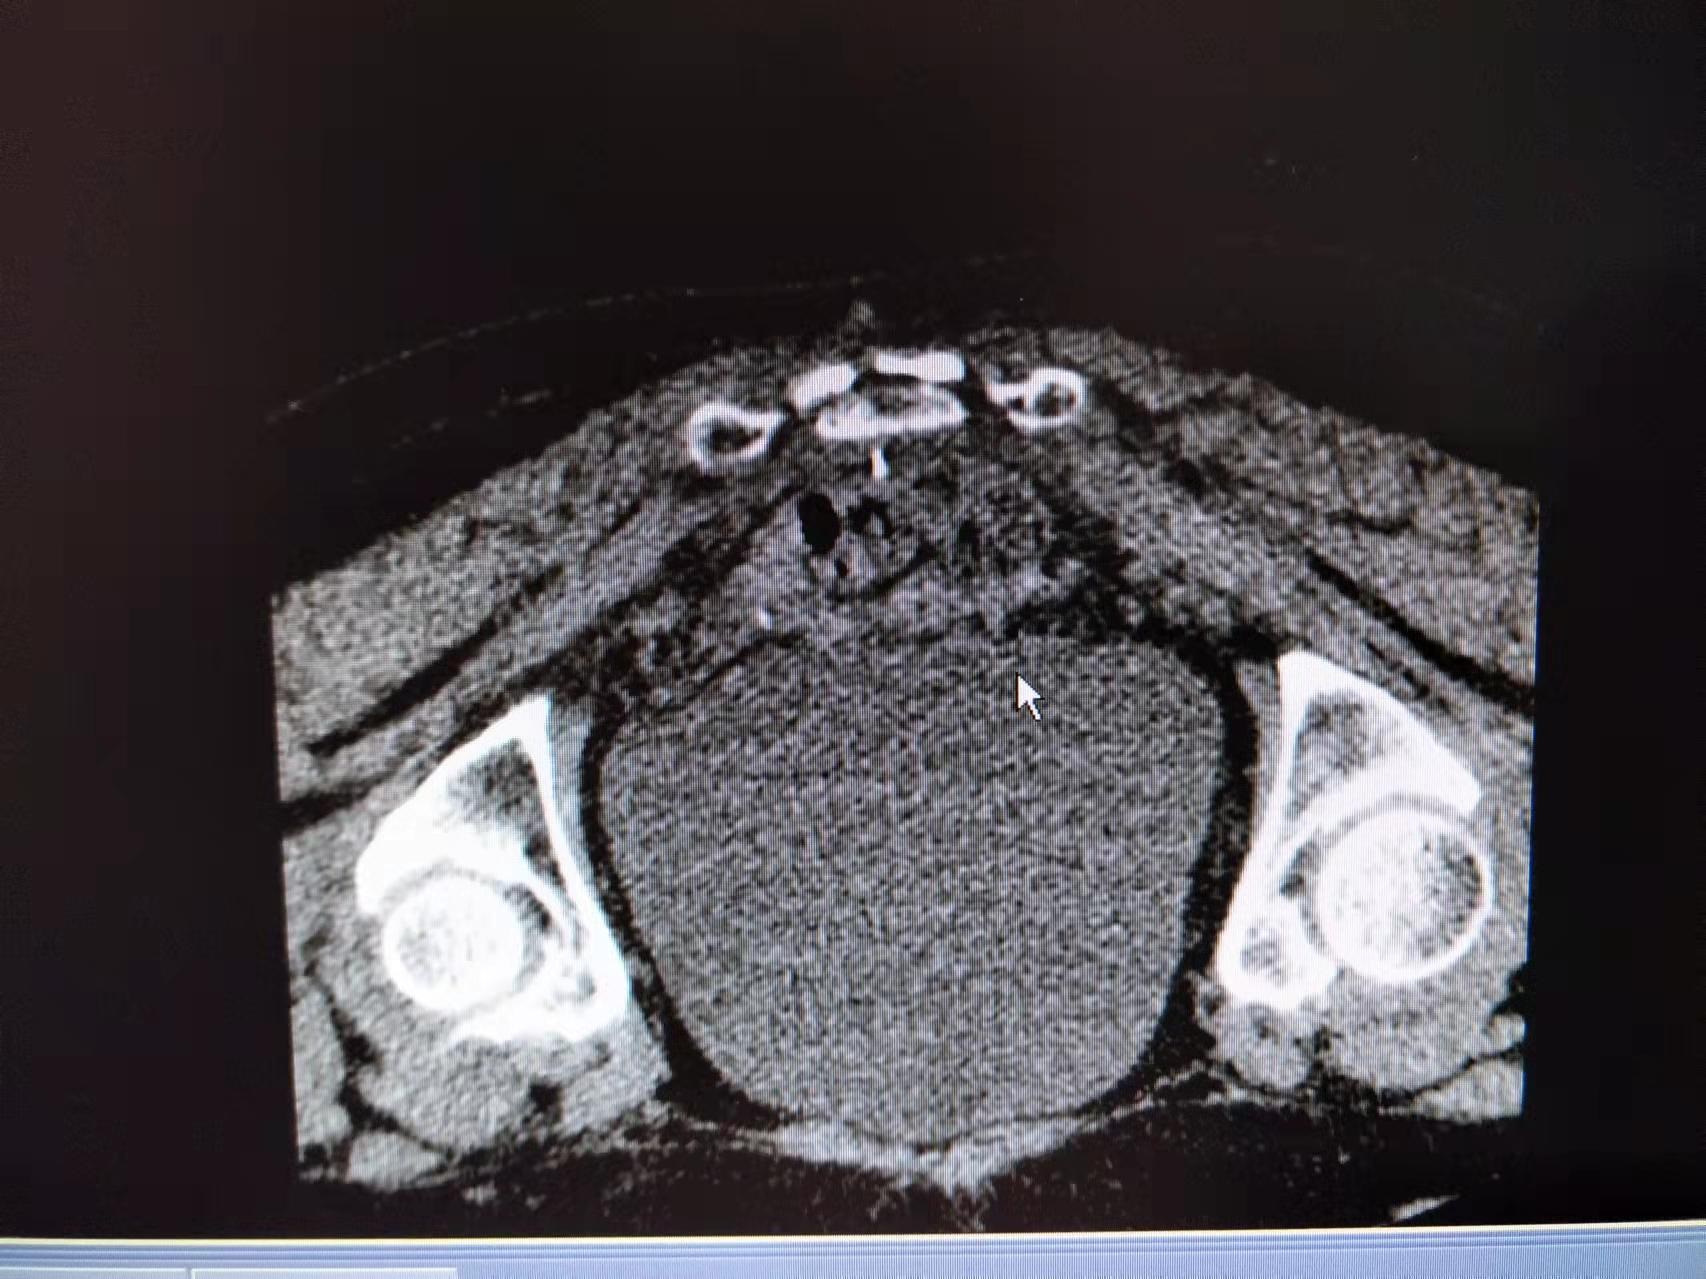

腰椎间盘突出症的患者发病时往往痛不欲生,特别是急性发作期,我院疼痛科通过骶管治疗和CT引导下侧隐窝治疗缓解腰间盘压力,解除神经根水肿及炎性症状,为此类广大病友带来了福音。

骶管治疗和CT引导下的侧隐窝治疗有着不开刀、损伤小、疗效确切的优点!

顽固性会阴痛难以启齿却困扰着很多病友,这是一例CT引导下精准化奇神经毁损治疗顽固性会阴痛,治疗后第二日便收获了病友大大的赞。